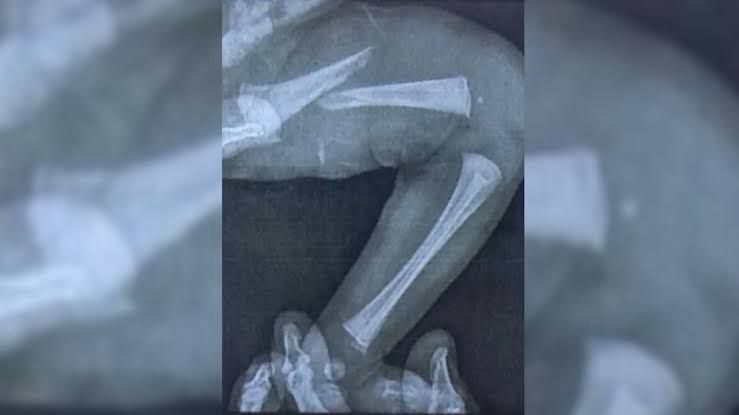

Fratura foi confirmada dois dias depois do teste

A fratura na perna da recém-nascida, ainda segundo a policial, foi confirmada dois dias depois do teste do pezinho, após os pais buscarem atendimento em duas diferentes unidades de saúde. O pai e a mãe da bebê moram no Tocantins e vieram para Goiás apenas para o parto, que foi realizado em Goiânia. As identidades deles não foram reveladas. Em decorrência da fratura, a recém-nascida está usando uma botinha de gesso.